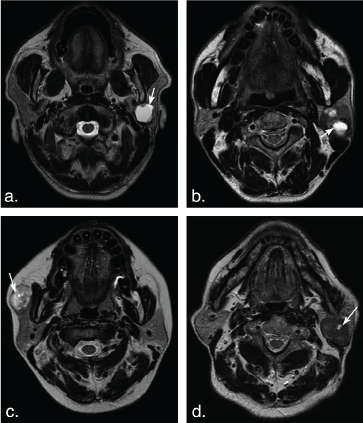

Figure 1: A 75-year-old man with basal cell adenoma in both superficial and deep lobes in the right parotid gland. Axial T2 weighted image (a) and axial T1 weighted image (b) show a well-defined, encapsulated, heterogeneous, lobulated tumor with irregular cystic area (arrowheads) and solid nodule (arrows). The solid portion of the tumor shows hypoinentse signal on T2 weighted and T1 weighted images and marked enhancement (arrow) compared with the surrounding parotid gland on axial contrast-enhanced fat-suppressed T1 weighted image (c) but mild enhancement (arrow) on coronal non-fat suppressed T1 weighted image (d) (arrows). View Figure 1

Figure 2: A 53-year-old man with basal cell adenoma in the deep lobe of the left parotid gland. Axial T2 weighted image (a) and T1 weighted image (b) shows a well-defined, ovoid solid-looking tumor (arrows). The tumor shows slight hypointense signal on T2 weighted image and T1 weighted image, marked enhancement (arrow) on axial contrast-enhanced fat-suppressed T1 weighted image (c) but mild enhancement (arrow) on coronal non-fat suppressed T1 weighted image (d). View Figure 2

The solid portion of tumors in 7 of 9 BCAs (77.78%) and 8 of 62 PAs (12.90%) were hypointense on T2 weighted imaging. Two of 9 BCAs (22.22%) and 43 of 62 PAs (69.36%) showed mixed hyper- and hypointense, and 11 of 62 PAs (11.74%) showed hyperintense on T2 weighted imaging (Figure 4 and Figure 5). No lesion has hyperintense signal in BCAs and WTs on T2 weighted imaging (Figure 1, Figure 2, Figure 3, Figure 4, Figure 5 and Figure 6). There was significant difference between BCAs and PAs (P < 0.001).

Enhancement of tumor solid portion on the delayed phase of fat-suppressed contrast-enhanced T1 weighted imaging was significantly different between BCAs and WTs (P < 0.001). All lesions of BCAs and 43 of 62 (69.35%) PAs showed marked enhancement, while only 3 in 58 WTs were markedly enhanced (Figure 1, Figure 2, Figure 3, Figure 4, Figure 5 and Figure 6). No significant difference was found between BCAs and PAs (P = 0.0124).